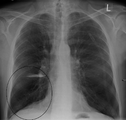

قد يفيد تصوير الصدر بالأشعة السينية والعد الدموي الشامل في استبعاد أسباب أخرى في وقت التشخيص.[52] والسمات المميزة للأشعة السينية هي التمدد الشديد للرئتين، وانبساط الحجاب الحاجز، وزيادة حيز الهواء خلف القص، والأمراض الجلدية، في حين أنها قد تساعد في استبعاد أمراض الرئة الأخرى مثل ذات الرئة ووذمة الرئة أو الاسترواح الصدري.[53] يمكن لصورة الصدر عالية الوضوح باستخدام التصوير المقطعي المحوسب بالأشعة السينية أن تبين توزيع النفاخ الرئوي في جميع أنحاء الرئتين ويمكن أيضاً أن تكون مفيدة في استبعاد أمراض الرئة الأخرى.[11] إذا لم يكن مخططاً لإجراء عملية جراحية، فهذا نادراً ما يؤثر على العلاج.[11] ويتم استخدام غازات الدم الشرياني لتحديد مدى الحاجة إلى الأكسجين؛ ويوصى به لمن يُتوقع أن يكون حجم الزفير القسري لديهم1 أقل من 35%، والذين لديهم تشبع أكسجين محيطي أقل من 92% والذين تظهر لديهم أعراض قصور القلب الاحتقاني.[10] في مناطق العالم التي يشيع فيها نقص مضاد التريبسين ألفا-1، يجب أن يوضع في الاعتبار اختبار الأشخاص المصابين بمرض الانسداد الرئوي المزمن (خاصة من هم دون سن 45 ولديهم نفاخ رئوي يؤثر على الأجزاء السفلية من الرئتين).[10]

فقاعة رئة كما تبدو عند تصوير الصدر بالأشعة السينية لدى شخص يعاني من داء الانسداد الرئوي المزمن الحاد